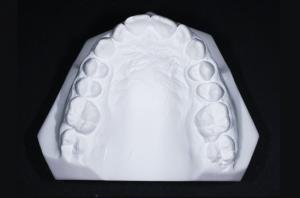

Si un traitement orthodontique est indiqué et que le moment est adéquat, nous allons réaliser un bilan orthodontique qui comprend :

• Des empreintes dentaires pour obtenir des moulages d’étude

À partir des éléments de ce bilan orthodontique, le praticien va pouvoir analyser les données cliniques, les photos, les radiographies pour une analyse céphalométrique et les moulages pour établir un diagnostic précis et proposer un traitement adapté.